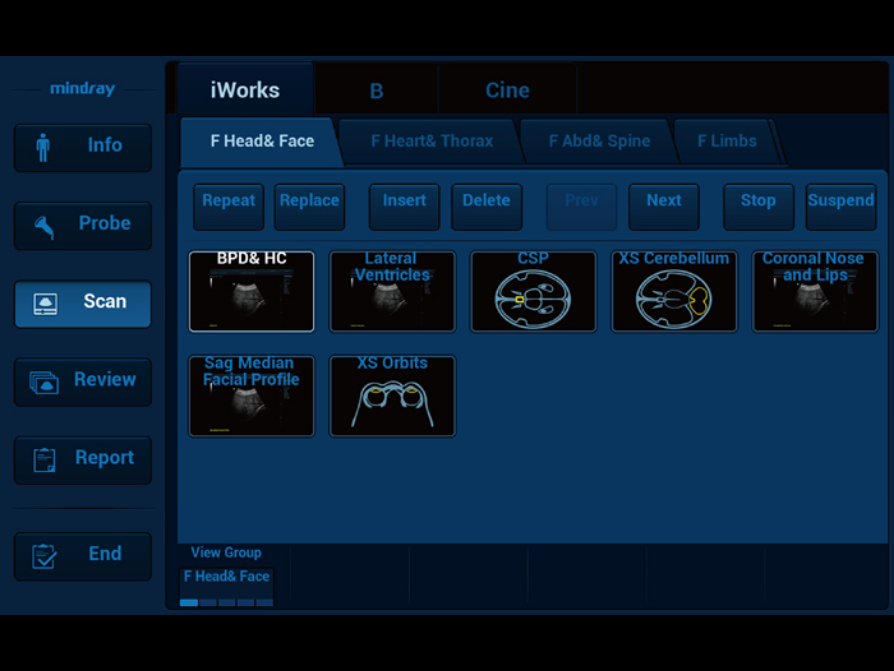

The flexible and customizable exam protocol tool helps to improve exam consistency and productivity by automating many repetitive actions, and to ensure exam completeness with user-friendly layout.